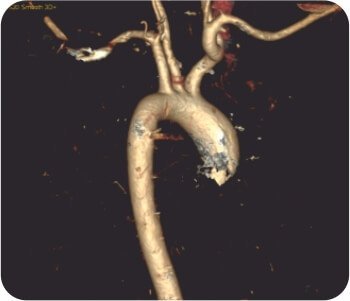

থোরাসিক এনজিওগ্রাম সহ CT বুকে হাইপারট্রফিড কোলাটারাল ধমনী সহ দ্বিপাক্ষিক গহ্বরের ক্ষত প্রকাশ করে যা প্রধানত ডান উপরের লোব গহ্বর সরবরাহ করে। FOB করা হয়েছে ডান উপরের লোব ব্রঙ্কাস থেকে সক্রিয় রক্তপাত দেখায়।

সিটি থোরাসিক এনজিওগ্রাফ